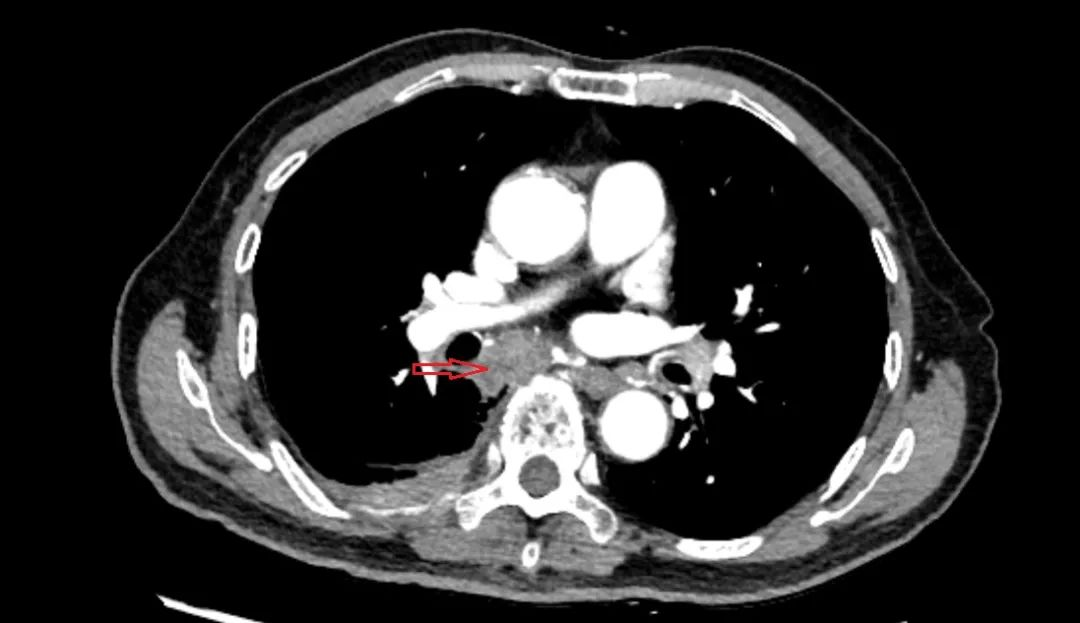

病例二

患者胸部增强CT发现右下肺肿物,患者高龄(>80岁)、肺功能差、家属十分抗拒经皮肺穿刺活检,遂于全麻下右下肺肿物穿刺,确诊鳞癌,术后患者无诉不适。